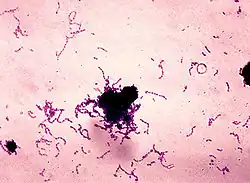

Bacteria

The most common bacteria associated with dental cavities are the mutans streptococci, most prominently Streptococcus mutans and Streptococcus sobrinus, and lactobacilli. However, cariogenic bacteria (the ones that can cause the disease) are present in dental plaque. They are usually in concentrations too low to cause problems unless there is a shift in the balance.[27] This is driven by local environmental change, such as frequent sugar intake or inadequate biofilm removal (toothbrushing).[28] If left untreated, the disease can lead to pain, tooth loss and infection.[29]

The mouth contains a wide variety of oral bacteria. Only a few specific species of bacteria are believed to cause dental caries: Streptococcus mutans and Lactobacillus species among them. Streptococcus mutans are gram-positive bacteria that constitute biofilms on the surface of teeth. These organisms can produce high levels of lactic acid following fermentation of dietary sugars and are resistant to the adverse effects of low pH, properties essential for cariogenic bacteria.[24] As the cementum of root surfaces is more easily demineralized than enamel surfaces, a wider variety of bacteria can cause root caries, including Lactobacillus acidophilus, Actinomyces spp., Nocardia spp., and Streptococcus mutans. Bacteria collect around the teeth and gums in a sticky, creamy-coloured mass called plaque, which serves as a biofilm. Some sites collect plaque more commonly than others, for example, sites with a low rate of salivary flow (molar fissures). Grooves on the occlusal surfaces of molar and premolar teeth provide microscopic retention sites for plaque bacteria, as do the interproximal sites. Plaque may also collect above or below the gingiva, where it is referred to as supra- or sub-gingival plaque, respectively.

In the 1890s, W. D. Miller conducted a series of studies that led him to propose an explanation for dental caries that was influential for current theories. He found that bacteria inhabited the mouth and that they produced acids that dissolved tooth structures when in the presence of fermentable carbohydrates.[171] This explanation is known as the chemoparasitic caries theory.[172] Miller's contribution, along with the research on plaque by G. V. Black and J. L. Williams, served as the foundation for the current explanation of the etiology of caries.[160] Several of the specific strains of lactobacilli were identified in 1921 by Fernando E. Rodríguez Vargas.

In 1924 in London, Killian Clarke described a spherical bacterium in chains isolated from carious lesions which he called Streptococcus mutans. Although Clarke proposed that this organism was the cause of caries, the discovery was not followed up. Later, in 1954 in the US, Frank Orland working with hamsters showed that caries was transmissible and caused by acid-producing Streptococcus thus ending the debate whether dental caries were resultant from bacteria. It was not until the late 1960s that it became generally accepted that the Streptococcus isolated from hamster caries was the same as S. mutans.[173]